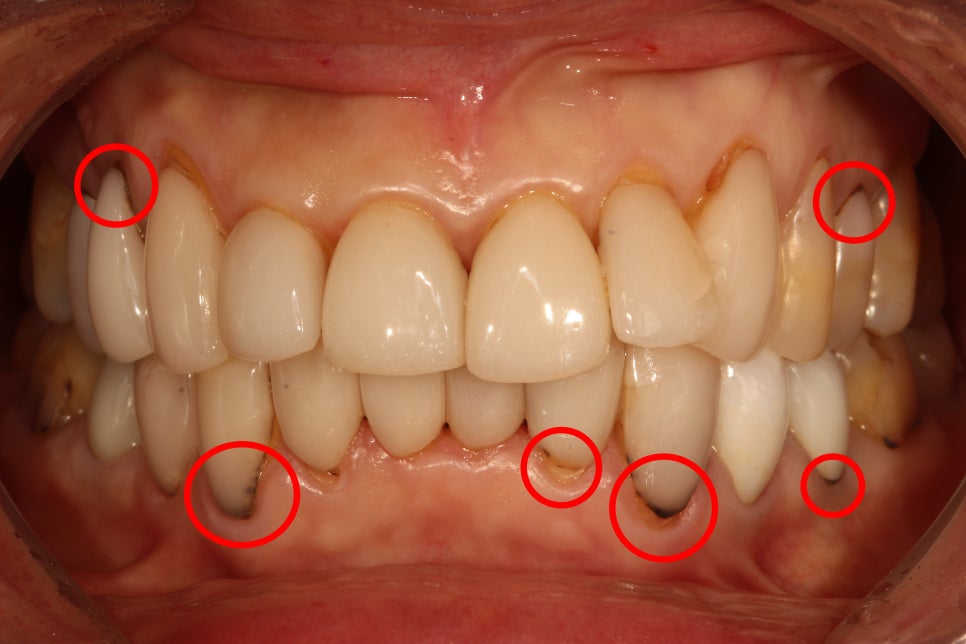

1) MINISH vs. Veneers (Laminates): The Key Difference Is “Where They Can Be Used”

MINISH and veneers can differ by material, fabrication method, and underlying technology. But the most practical difference for patients is which teeth they can be applied to, because the treatment goals are not the same.

- MINISH: can be applied more broadly—from front teeth to molars

- Veneers (laminates): typically used mainly for front teeth

Treatment goal

- MINISH: focused on restoring and reinforcing weakened or damaged enamel (your tooth’s natural protective layer). When enamel is restored, teeth often appear brighter and healthier in a natural-looking way.

- Veneers (laminates): primarily focused on aesthetic redesign of the front tooth surface—brighter shade, improved alignment appearance, and a “smile line” makeover.